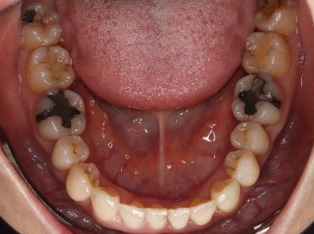

乱ぐい歯、でこぼこがとても酷い状態になります。歯が前後的に重なってしまっている、八重歯になっているなどがこのジャンルに入ります。

顎の大きさと歯の大きさのギャップが大きく、時には歯を抜かないと矯正治療ができない場合もあります。当院では治療期間が長くなるが抜かない治療方針など、一つの治療プランだけでなく、さまざまな可能性の治療方針を説明させて頂くよう心掛けております。こういった考え方はインフォームド・チョイスと言われ近年大切にされている考え方と言われております。

治療前

治療終了前